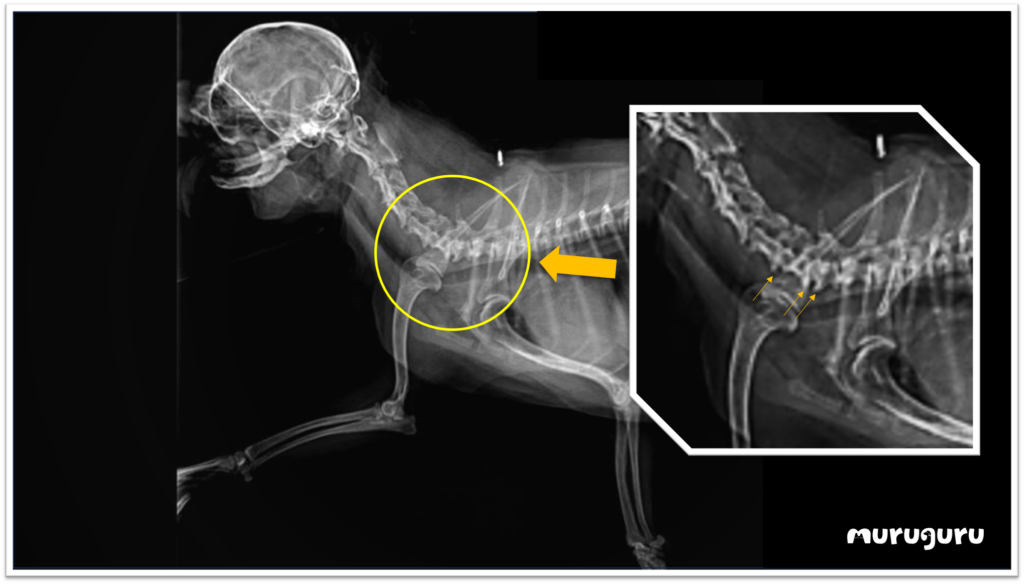

波波是一隻已達13歲高齡的松鼠狗,長期受到松鼠狗常見的關節問題困擾。大約半年前,牠突然右手無法彈動,令主人擔心關節問題可能惡化,於是迅速向獸醫Dr. Doris求醫,進行X光檢查,結果發現波波的頸椎出現了骨刺,這正是導致右手癱瘓的元兇。

在老年貓狗中,骨刺是一種相當常見的毛病,通常在兩塊骨骼的交界處出現骨質增生。根據X光影像,波波的第五至七節頸椎出現了微小的骨刺,雖然數量不多,但突出來壓迫了傳遞去右手的神經線,對神經傳遞造成影響,結果右手失去了神經反射,導致癱瘓的情況發生。